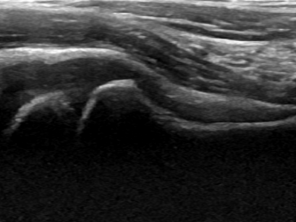

四、超声检查在儿童髋关节滑膜炎中的应用[2]

超声检查是一种无创、无辐射的检查方法,对于儿童髋关节滑膜炎的诊断具有重要价值。通过超声检查,可以观察到髋关节内的积液情况、滑膜的厚度以及关节周围组织的病变情况,为临床诊断提供依据。

3. 能够观察关节内积液、滑膜厚度和形态等细节,为诊断提供依据。